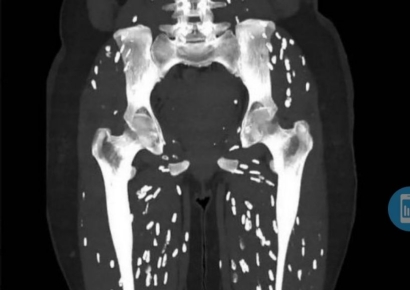

"가장 끔찍한 CT영상"…다리에 '쌀알 모양 기생충' 득실 왜?

미국의 한 대학병원 응급실 의사가 덜 익은 돼지고기를 먹고 기생충에 감염된 환자의 컴퓨터 단층촬영(CT) 사진을 공개하며 주의를 당부했다. 28일(현지시간) 데일리메일에 따르면 미국 플로리다 대학교 의대 병원 응급실 의사인 샘 갈리 박사는 지난 25일 사회관계망서비스(SNS) X(옛 트위터)에 기생충에 감염된 환자의 다리 CT 사진을 올렸다. 갈리 박사는 이 사진에 "내가 본 것 중 가장 끔찍한 CT 영상"이라는 설명을 달았다.